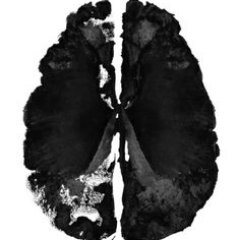

🍄 Studies showing comparisons of images of patients’ brains before, and one day after they received the ‘magic’ treatment revealed changes in brain activity that were associated with marked and lasting reductions in depressive symptoms. Learn more at the link in our bio!